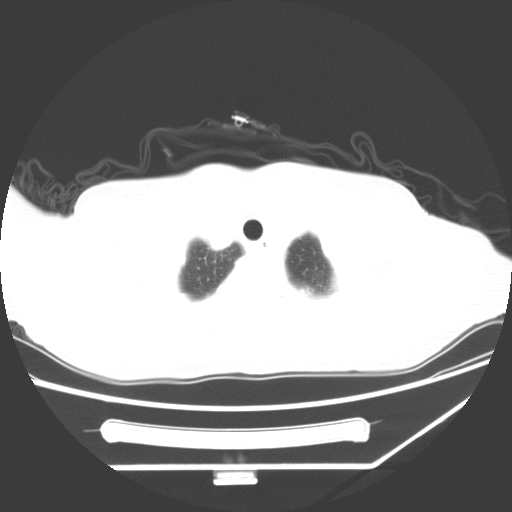

标题: CT25393:病人45岁,咳嗽,吐黄痰带血丝,发热,胸闷月余 [打印本页]

标题: CT25393:病人45岁,咳嗽,吐黄痰带血丝,发热,胸闷月余

1、左肺中央型肺癌并双肺弥漫性转移   2、双肺部感染    3、肺大泡     4、左侧胸腔积液

双侧肺弥漫性病变,可见“空泡征”及“蜂窝征”,考虑肺泡癌可能性大,左侧胸腔积液,考虑胸膜受累可能!

考虑肺泡癌,建议排除感染。

考虑肺泡癌

1)不排除肺泡癌可能。2)左侧胸腔积液。